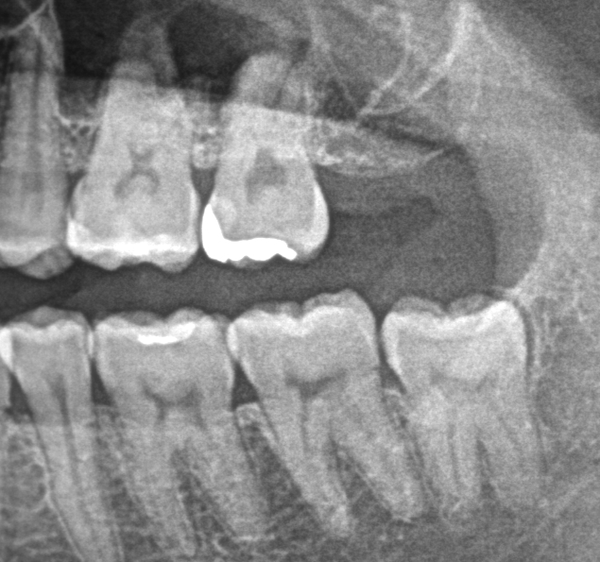

実際には、右上歯に関しては癒合歯といわれる2番目の歯と3番目の歯がくっついてしまっている状態で、サイズも通常より大きく形態も通常とは異なり変色もしていました。

今回の場合では、2本の歯が1本に癒合している状況であり、変色もあったため、被せ物の治療を行うことになりました。

人間の歯の形態、位置、並び方などは一人として同じものはありませんし、正解もありません。今回の症例でも癒合はしていましたが、患者さんへの不都合は特になく、何度か樹脂で治療を行っていました。しかし、先頭の2本の歯をかぶせるタイミングで一緒にきれいにセラミックで治したいとのご希望でした。樹脂の詰め物は手軽に治療できる反面、経年的な色の変化や材料の劣化などが起きやすく、長期間使うことは難しい場合もあります。